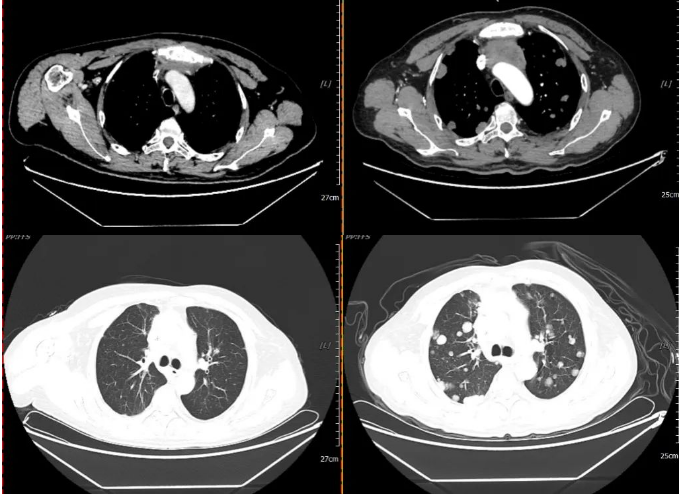

2020-07-03 2021-02-20

与2020年7月3日片对比:两肺多发异常结节较前明显增多、增大(原约3.2×2.1,现约3.9×3.0cm);纵膈前间隙、纵隔内及两肺门多发增大淋巴结较前部分增大(原约5.2×3.4,现约6.7×4.0cm)并胸骨受累(新出),邻近上腔静脉及左头臂静脉受累较前加重。